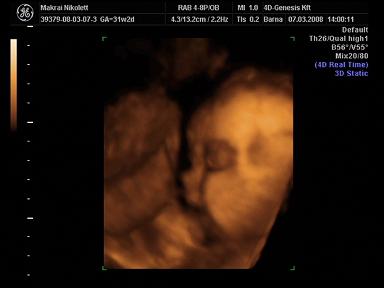

2008.03.07 19:48